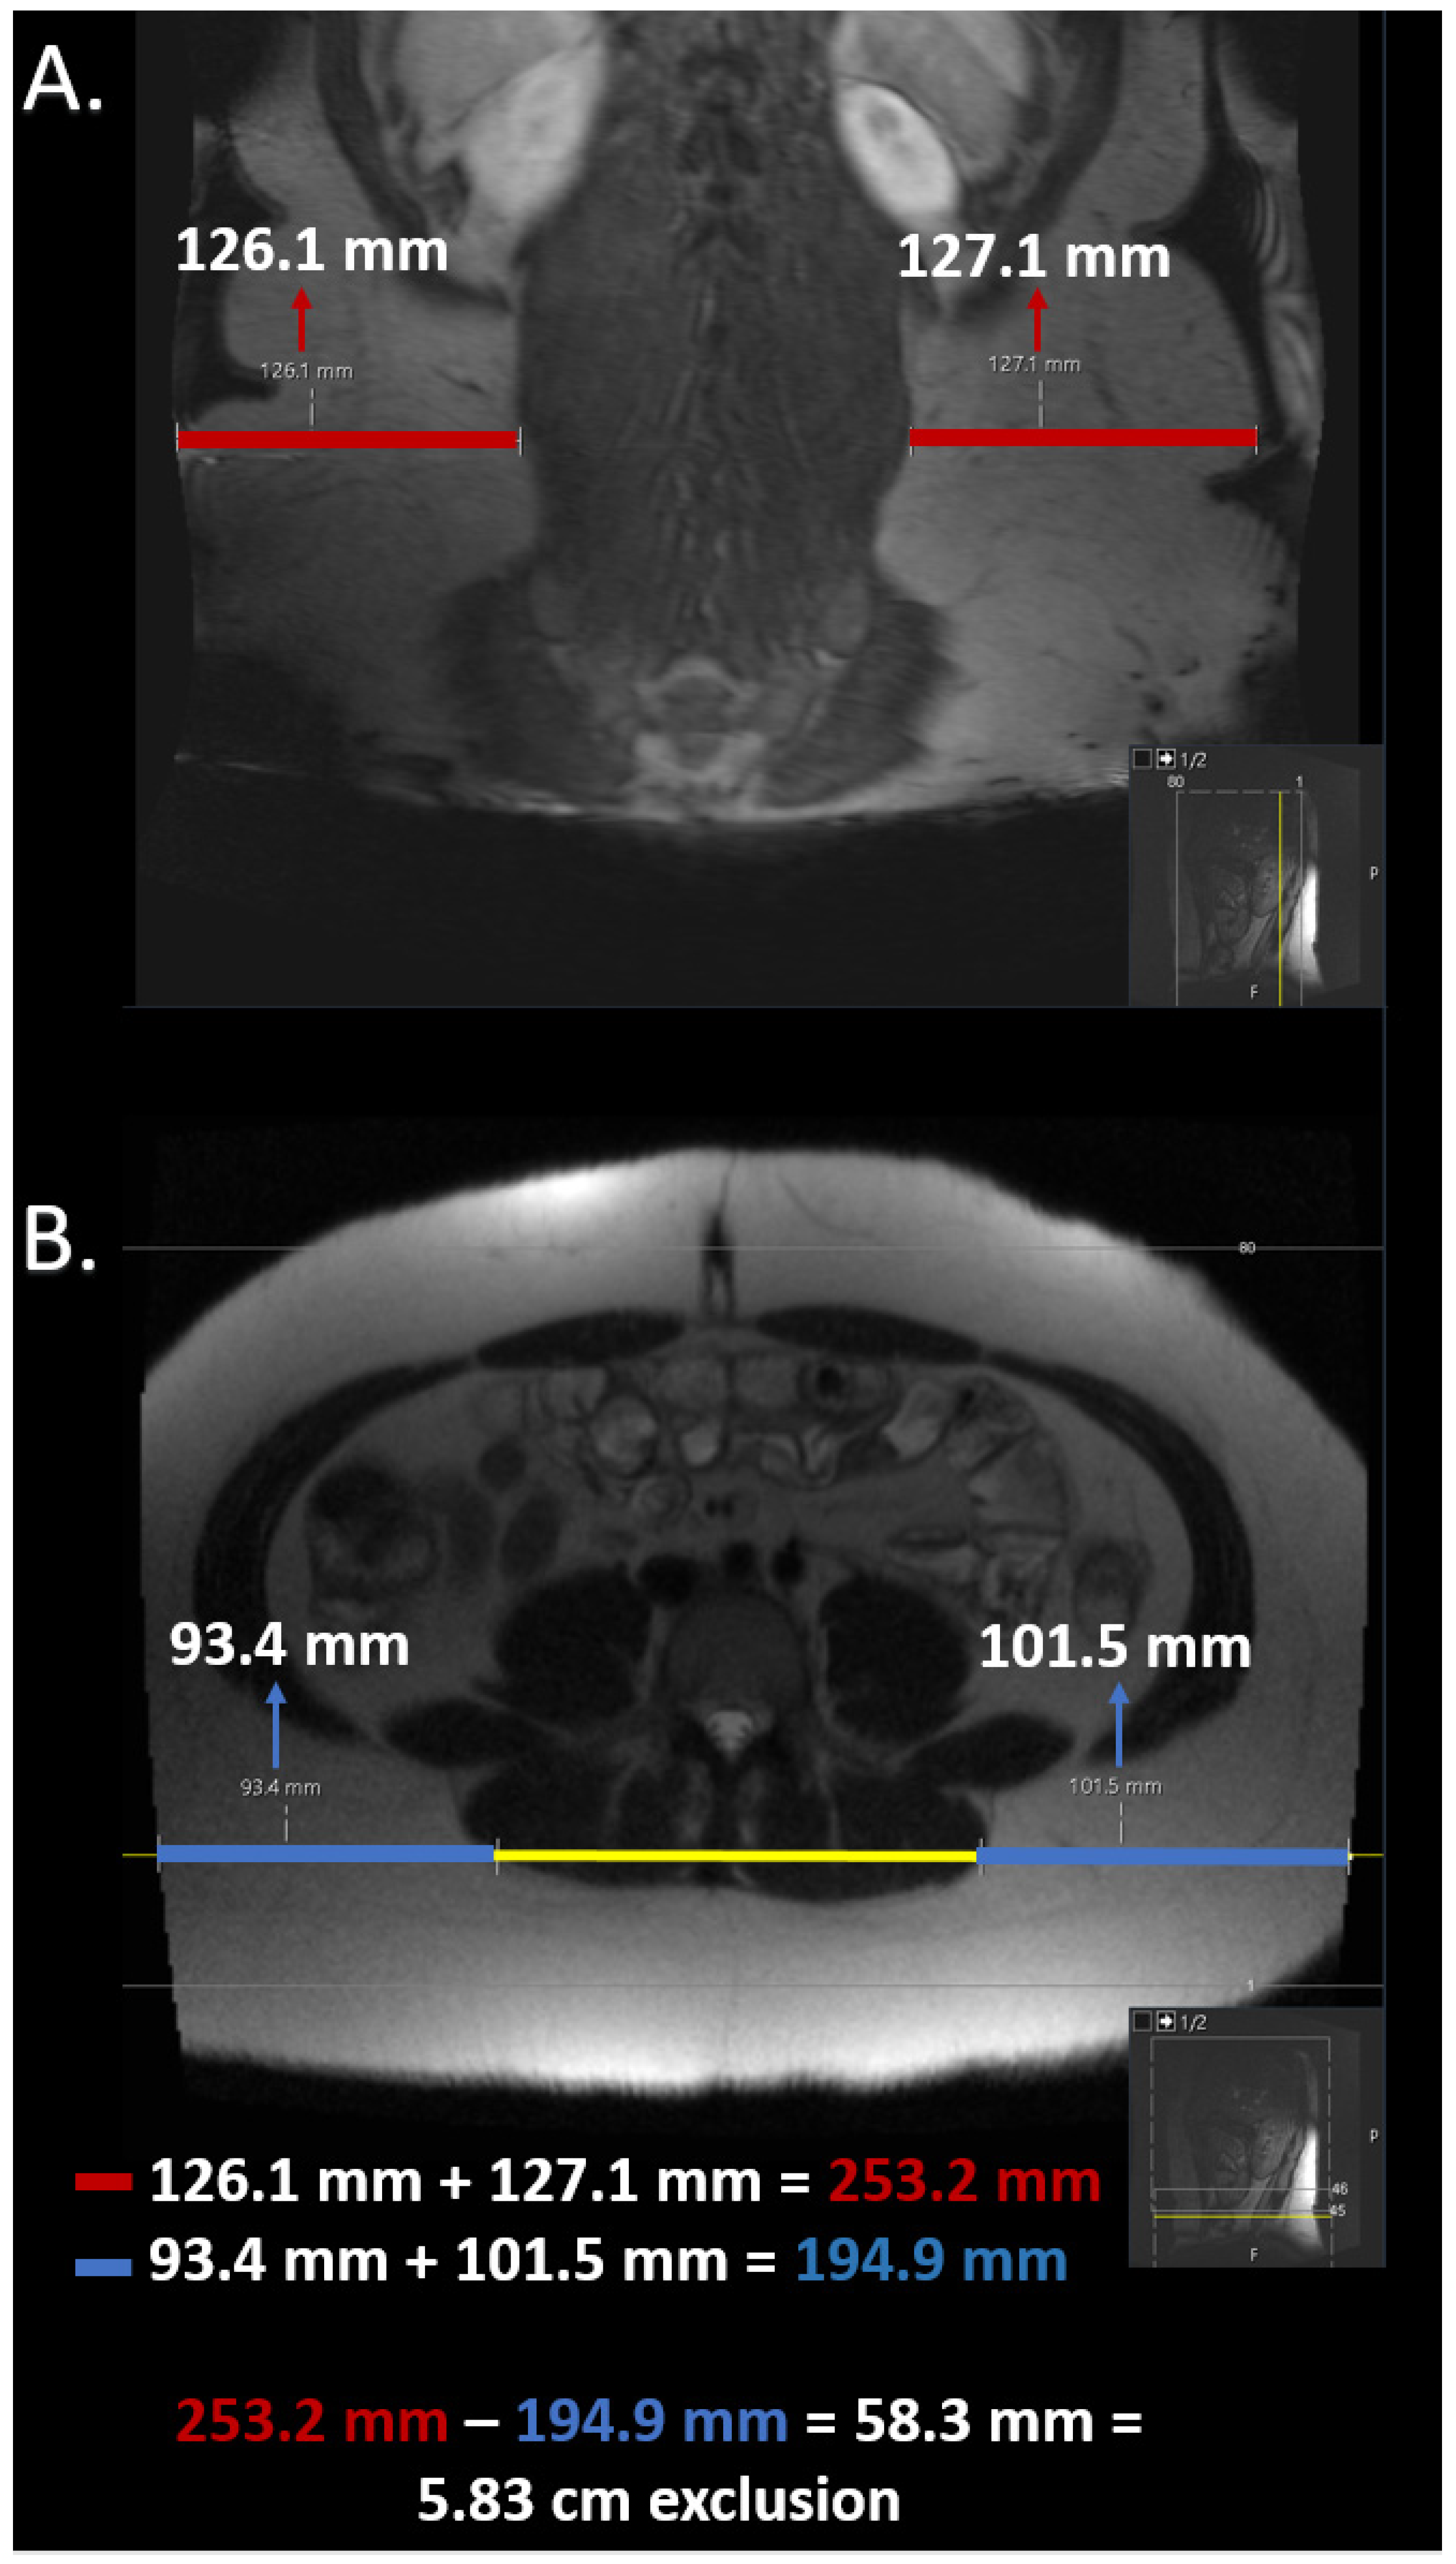

2.5. Estimation of Field of View Restriction